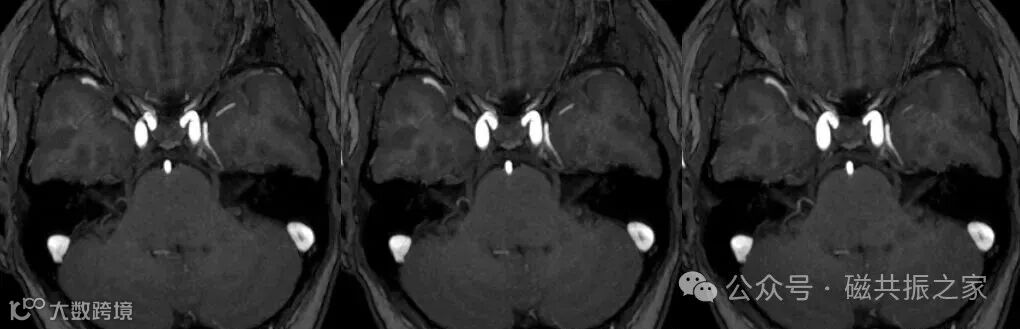

在使用3D TOF成像时,为了增加小血管的显示能力,建议不使用磁化传递技术和添加上下(头足)侧饱和带。

如在三叉神经痛的诊治方面,二者联合对于术前判断血管与神经关系具有极高准确率(灵敏度和特异度分别可高达100%和96%)。

但需要注意的是由于3D稳态自由进动序列会随着磁场的升高其对比度会下降,且伪影风险增加(1.5T选用,3.0T及以上慎用),所以首选基于自旋回波的3D 重T2序列。